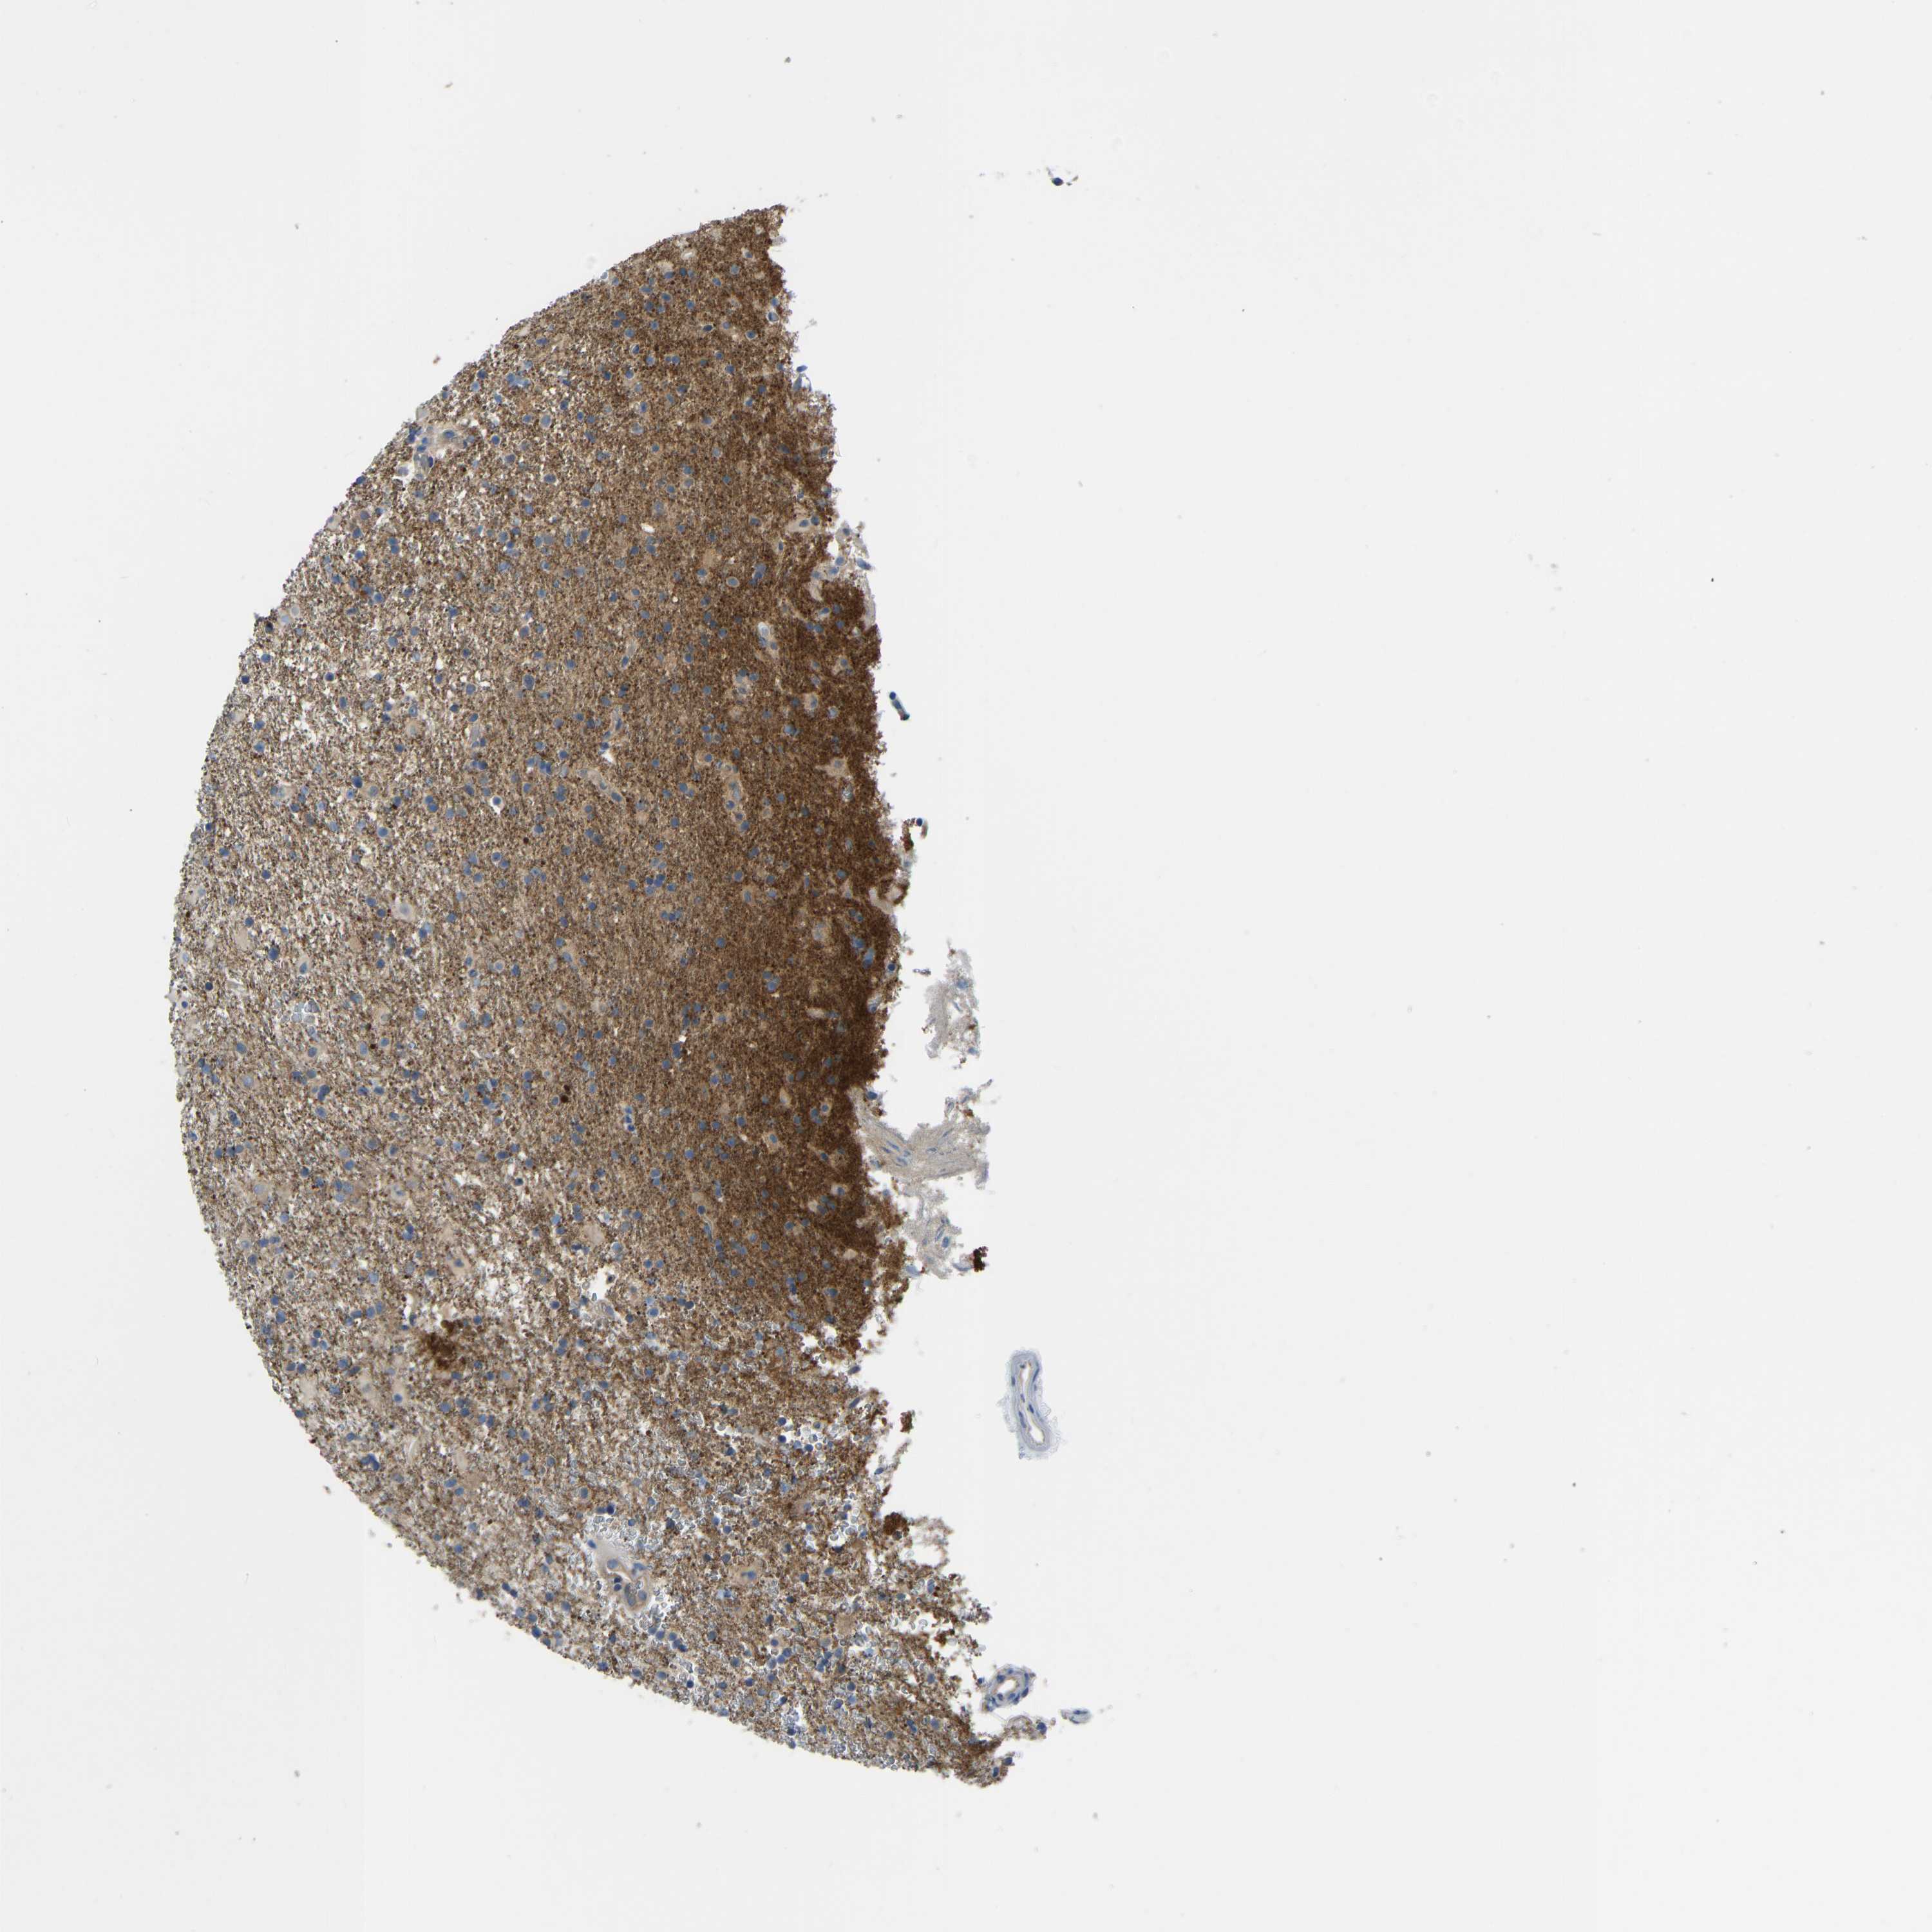

GLIOMA - Protein expressioni

A mouse-over function shows sample information and annotation data. Click on an image to view it in a full screen mode. Samples can be filtered based on level of antibody staining by selecting one or several of the following categories: high, medium, low and not detected. The assay and annotation is described here.

Note that samples used for immunohistochemistry by the Human Protein Atlas do not correspond to samples in the TCGA dataset.

Antibody stainingi

Antibody staining in the annotated cell types in the current human tissue is reported as not detected, low, medium, or high, based on conventional immunohistochemistry profiling in selected tissues. This score is based on the combination of the staining intensity and fraction of stained cells.

Each image is clickable and will lead to virtual microscopy that enables deeper exploration of all samples and also displays staining intensity scores, fraction scores and subcellular localization as well as patient and tissue information for each sample.

Antibody HPA012778

Antibody CAB018581

Staining

High

Medium

Low

Not detected

Intensity

Strong

Moderate

Weak

Negative

Quantity

>75%

75%-25%

<25%

None

Location

Nuclear

Cytoplasmic/membranous

Cytoplasmic/membranous,nuclear

Glioma, malignant, High grade

Glioma, malignant, Low grade